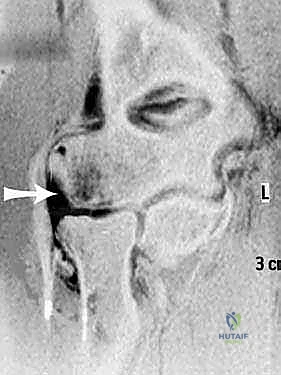

- التصوير بالرنين المغناطيسي (MRI): هو المعيار الذهبي لتصوير الأنسجة الرخوة. يستخدم الدكتور هطيف أجهزة رنين مغناطيسي عالية الدقة لتقييم مدى تمزق مركب الرباط الجانبي الوحشي (LUCL)، بالإضافة إلى فحص الغضاريف والأوتار المحيطة. في بعض الحالات المعقدة، قد يتم حقن صبغة داخل المفصل (MR Arthrogram) لزيادة دقة التشخيص.